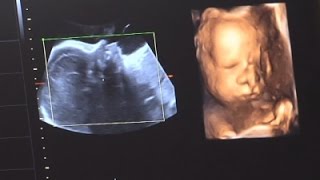

Amazing Animation of a Fetus Growing in the Womb